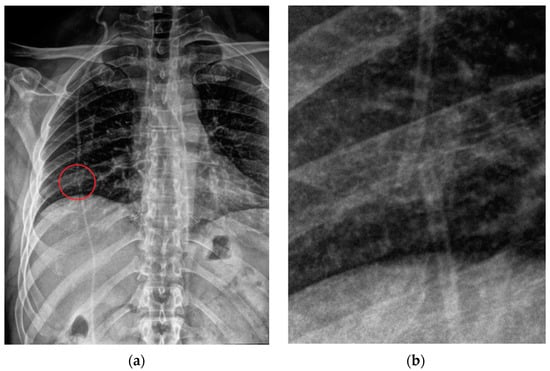

4. Airway Devices

4.1. Endotracheal Tubes